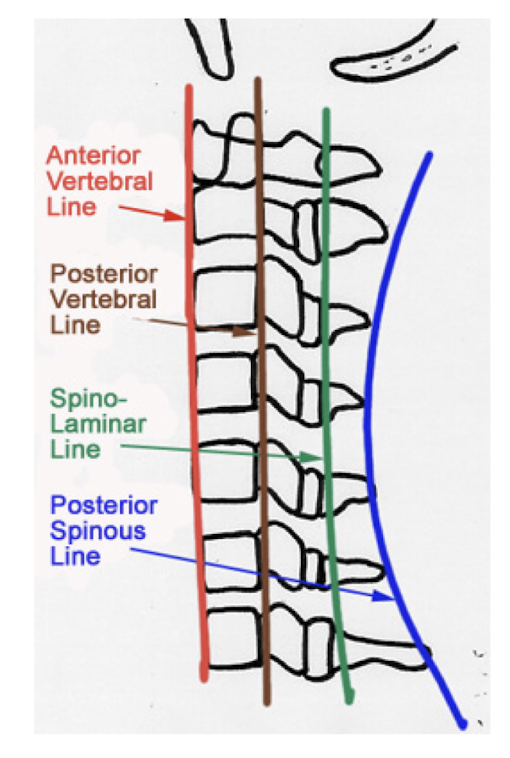

Label these 4 Lines? (C/S)